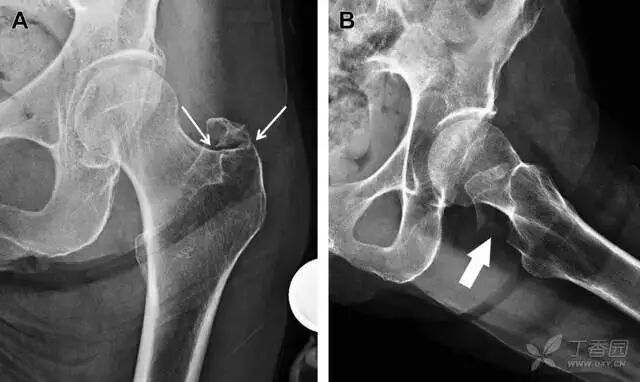

图 1 长跑运动员股骨隐匿性、应力性骨折。A 为髋部正位 片,虽未见明显骨折,但股骨颈基底部可见一模糊的线性硬化带(箭头)B 为 MRI 冠状位 STIR 序列扫描,示股骨颈应力侧可见一线性低密度信号影,周围包绕骨髓水肿的高密度影

从这个案例来看,长期运动的患者,如果出现髋部疼痛,X 线即使无特殊表现,也应考虑应力性骨折的可能性。

髋臼骨折

髋臼骨折最常见的类型是髋臼后壁骨折,几乎占髋关节骨折的 1/4,且常常合并髋关节后脱位。由于骨性结构重叠,可能肉眼看上去觉得非常轻微的骨折,事实却并非如此。髋臼后缘中断常常是髋臼后壁骨折的一个特征(图 2)。

图 2 为髋臼后壁骨折伴髋关节脱位患者。A 右侧髋关节 X 线片示股骨头后方可见一骨折线(箭头),髋臼后缘中断。B 左侧髋关节 X 片对照可见髋臼后缘连续(箭头)。C  CT 三维重建图像示髋臼后壁缺损,可见旋转、移位的骨折块(箭头)